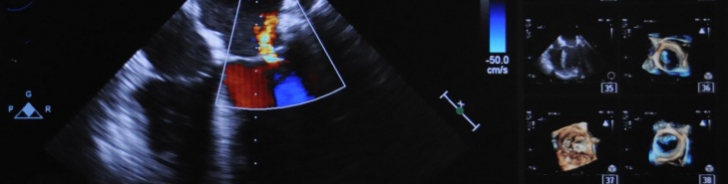

Valve Surgery

• Valve Replacement in Median Sternotomy or Mini-Thoracotomy

• Art or Bioprosthesis

• Seamless Flaps

• Heart Valve Reconstruction also Minimally Invasive

• Catheter Intervention Replacement (TAVI)